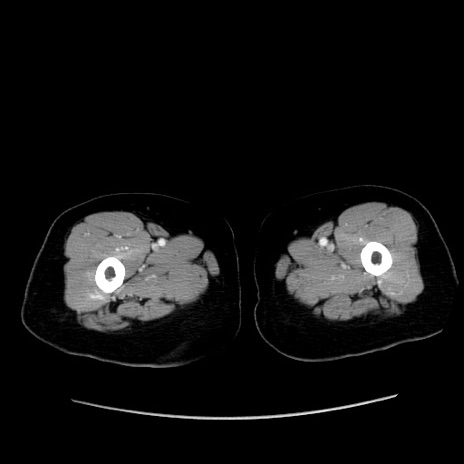

症例19(横断像)

【症例】80歳代女性

【主訴】下腹部痛

【現病歴】約8時間前より下腹部痛の出現あり、救急外来受診。

【既往歴】両側付属器切除

【身体所見】意識清明、下腹部正中に手術痕あり、その部位に一致して圧痛と反跳痛あり。腸蠕動音は亢進。

【データ】WBC 9300、CRP 0.15